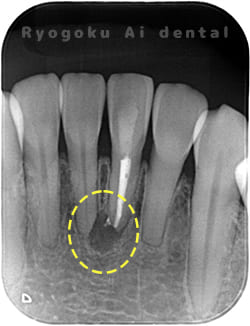

Case10

- 原因

- 下顎前歯部歯根嚢胞

- 治療内容

- 歯根端切除法

- 治療費用

- ¥77,000×2

他院で歯根端切除術を行ったが、良くならないとのことで、ご来院された患者様です。再根管治療後、サイナストラクトが消失しなかったため、歯根端切除術を行いました。現在、一年経過しておりますが、再発もせず、経過良好です。

<リスク・副作用>

外科手術のため、術後に出血、痛みや腫れ、違和感を伴います。口腔内の状態によっては適応できないことがあります。歯根端切除で治らなければ抜歯を検討しなくていけない場合もあります。